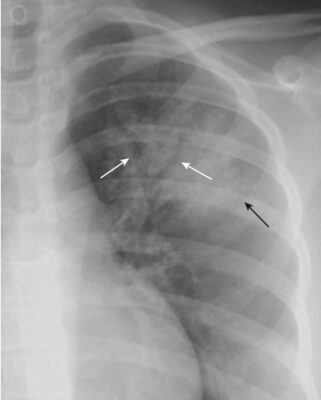

- Viêm phổi có thể có khí phế đồ nếu phế quản đó không chứa đầy dịch viêm.

- Có nhiều khả năng thấy hình ảnh phế quản chứa khí (khí phế đồ) khi viêm phổi liên quan đến phần trung tâm của phổi gần rốn phổi. Gần vùng ngoại vi của phổi, các phế quản thường quá nhỏ để có thể nhìn thấy được (Hình 1).

- Hãy nhớ rằng bất kỳ chất dịch hoặc mật độ mô mềm nào thay thế cho khí bình thường trong khoảng chứa khí cũng có thể tạo ra dấu hiệu này; do đó, khí phế đồ không đặc hiệu cho bệnh viêm phổi.

- Ngoại trừ sự xuất hiện của khí phế đồ, viêm phổi khoảng chứa khí thường đồng nhất về đậm độ (Hình 2).